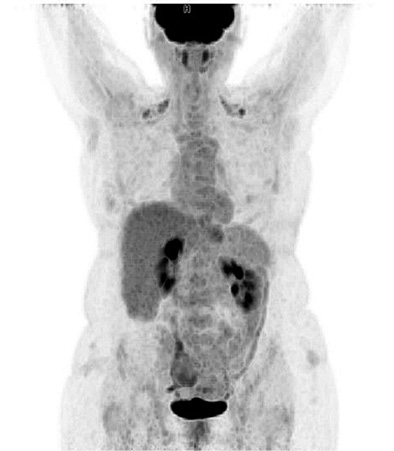

The patient was referred to a hematologist for proper staging and therapy. The positron emission tomography-computed tomography (PET/CT) scan showed a normal findings with low metabolic activity in the area of the wound infection (Figure 4). Bone marrow biopsy was negative. According to the Lugano score [7], the patient was diagnosed with Stage I of the disease.

Seven cycles of R-CHOP (rituximab, cyclophosphamide, doxorubicin, vincristine, and prednisolone) regimen were given to the patient as the first line of treatment. Post-chemotherapy PET/CT scan presented with normal findings. The patient is still in complete remission after the combined treatment with surgery and chemotherapy and regular future checkups are scheduled.

Figure 4. PET/CT scan with normal finding